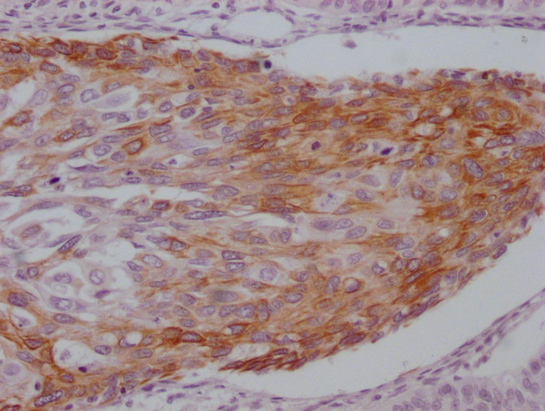

IHC image of CSB-MA785224 diluted at 1:100 and staining in paraffin-embedded human breast cancer performed on a Leica BondTM system. After dewaxing and hydration, antigen retrieval was mediated by high pressure in a citrate buffer (pH 6.0). Section was blocked with 10% normal goat serum 30min at RT. Then primary antibody (1% BSA) was incubated at 4°C overnight. The primary is detected by a Goat anti-mouse IgG polymer labeled by HRP and visualized using 0.05% DAB.

IHC image of CSB-MA785224 diluted at 1:100 and staining in paraffin-embedded human cervical cancer performed on a Leica BondTM system. After dewaxing and hydration, antigen retrieval was mediated by high pressure in a citrate buffer (pH 6.0). Section was blocked with 10% normal goat serum 30min at RT. Then primary antibody (1% BSA) was incubated at 4°C overnight. The primary is detected by a Goat anti-mouse IgG polymer labeled by HRP and visualized using 0.05% DAB.